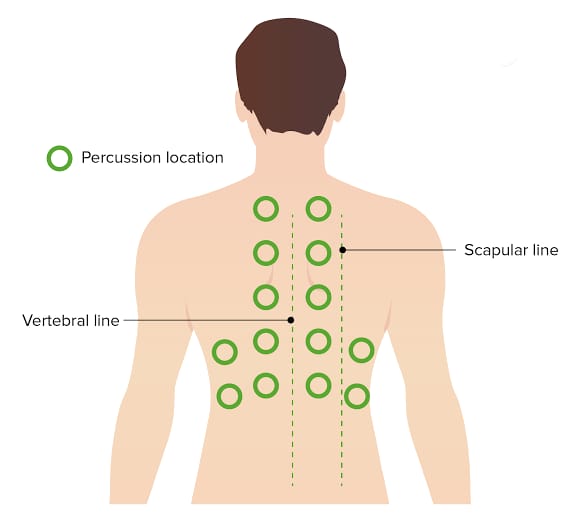

Percussion (પરકશન):

- રેસ્પાયરેટરી પરકશનમાં ચેસ્ટનું ટેપિંગ કરીને અન્ડરલાઇંગ સ્ટ્રકચરને અસેસ કરવામાં આવે છે જેથી ત્યાં એર, ફ્લુઇડ અથવા સોલીડ પ્રેઝન્ટ છે કે નહિ ચેક કરી શકાય.

- જેમાં એન્ટેરીઅર અને પોસ્ટેરીઅર ચેસ્ટને સાઇડ ટુ સાઇડ અને ટોપ ટુ બોટ્ટમ ટેપિંગ કરવામાં આવે છે અને તેના દ્વારા સાંભળવાં મળતા સાઉન્ડને નોટ કરવામાં આવે છે.

- આ ઉપરાંત રેસ્પાયરેટરી પરકશનમાં રેસ્પાયરેટરી એક્સકરસન નોટ કરવામાં આવે છે.

- રેસ્પાયરેટરી પરકશન એ લંગ ડેન્સિટીમાં જોવા મળતા ચેન્જીસને આઇડેન્ટીફાય કરવા તેમજ ન્યુમોનિયા, પ્લુરલ ઇફ્યુઝન જેવી કન્ડીશનને ડાયગ્નોસીસ કરવા માટે ઉપયોગી છે.